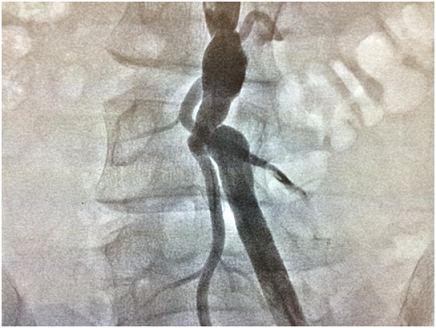

Xəstəyə ürək boşluqlarının kateterizasıyası qərarı verildi. Kateterizasiya zamanı sağ femoral arteriyanı punksiya məqsədilə palpasiya etdikdən nəbz qeyd edilmədi. Bu səbəbələ xəstənin sol femoral arteriya və venası punksiya olundu. Ürək boşluqları kateterizasiya olundu və xəstənin inoperabel olduğu qərarı verildi. Sağ femoral arteriyada nəbz qeyd olunmadığından xəstəyə abdominal aortaqrafiya olundu. Aortoqrafiya zamanı xəstənin sağ ümumi, daxili və xarici qalça arteriyalarının olmaması, aortanın bifurkasiya nahiyəsinin və sol ümumi qalça arteriyasının başlanğıcının fibromuskular distrofiyaya məruz qalması və sağ aşağı ətrafın sol daxili qalça, orta oma arteriyalarından gələn anastamozlar vasitəsilə qidalandığı aşkar edildi. Xəstə asimptomatik idi. Bu səbəbdən təqib qərarı verildi, heç bir müdaxilə olunmadı. (Şəkil 4,5,6)

Kollateral arteriyaların aşkar müşahidə olunması, sağ qalça arteriyasının güdülünün olmaması və xəstənin cavan olması müşahidə etdiyimiz patologiyanın anadangəlmə olduğuna dəlalət edir. Sağ ümumi qalça arteriyanın olmaması bu xəstədə asimptomatikdir, lakin gələcəkdə kollateral arteriyalar aterosklerotik dəyişikliklərə məruz qalarsa və ya FMD daha da irəliləyərsə xəstə simptomatik ola bilər.Finromuskular displaziyanı və sağ qalça arteriyasının olmamasını qalça arteriyanın aterosklerotik obliterasiyası, vaskulit, seqmental arterial mediolizis, requlyar arterial dalğalardan və Takayasu arteriitindən differensasiya etmək lazımdır.